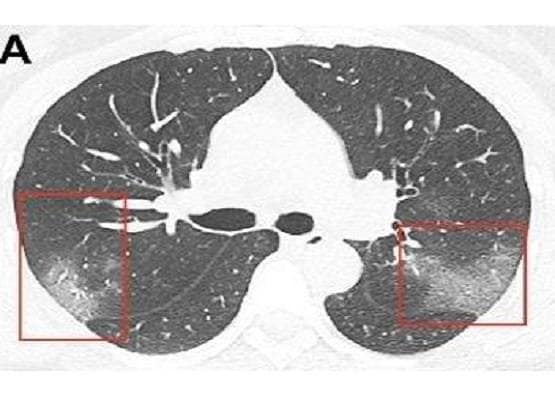

दरअसल, चीन के लंझाऊ स्थित एक अस्पताल में कोरोना वायरस संक्रमित 33 वर्षीय एक मरीज के सीने का X-Ray लिया गया. इसके बाद चौंकाने वाली तस्वीरें सामने आई. उन्होंने देखा कि सार्स की ही तरह कोरोना वायरस के भी लक्षण दिखाई दिए हैं. (Photo: Journal of Radiology)

जर्नल ऑफ रेडियोलॉजी के अनुसार डॉक्टरों द्वारा दिखाई गई  X-Ray रिपोर्ट में  फेफड़े के निचले हिस्से में कुछ दाग नजर आए. डॉक्टर्स ने इसे ground glass opacity बताया है.

(Photo: Journal of Radiology)

रेडियोलॉजिस्ट ने बताया कि जब उन धब्बों को ज़ूम कर देखा गया तो वे किसी शीशे के टुकड़ों की तरह नजर आए. ये साबित करते हैं कि वहां कुछ तरल पदार्थ इकठ्ठा हो गया है.